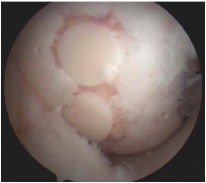

Fibrocartilage response to microfracture

Pluripotent marrow cells produce fibrocartilage to varying degree

- low stiffness and poor wear characteristics over time

- produces fibrocartilage

- results tend to deteriorate over time